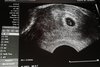

Takie malusie

Dzięki dziewczyny za wszystkie kciuki. Chyba się przydały. Lekarka zrobiła usg i powiedziała, że nie wie skąd krwawienie bo w macicy nie ma krwi. Dzisiaj już nic ze mnie nie leci. Widziałam na monitorze maluteńkie pikające serduszko! Dała mi nawet zdjęcie, całe 2,2 mm człowieczka :) Od dzisiaj leżę w domu i nie ruszam się w ogóle. Zwiększyłam dawkę progesteronu i liczę, że był to jednorazowy wybryk mojej macicy.